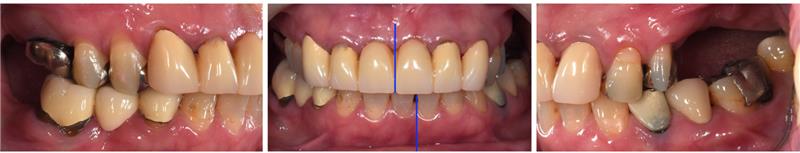

患者は40代女性で、上の歯が前に出ていることで噛みにくく、見た目も良くしたいとの理由で来院されました。奥歯の数は少なく、特に左上は大臼歯がありませんでした。上下の歯の真ん中のラインは大きくずれており、昔に入れた前歯の被せ物は変色し、審美障害を呈してました。(図1、2)

なにより大切なのは、最終的に必要な歯のセラミック治療を行い、見た目や細かい噛み合わせの構築を行う点です。